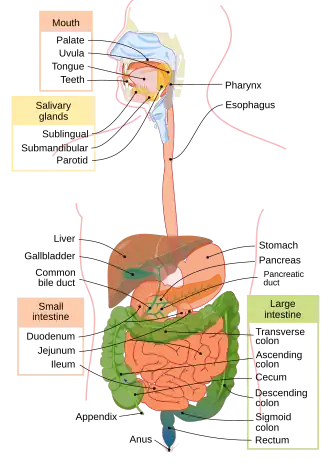

Digestive system

The digestive system consists of the mouth including the tongue and teeth, esophagus, stomach, (gastrointestinal tract, small and large intestines, and rectum), as well as the liver, pancreas, gallbladder, and salivary glands. It converts food into small, nutritional, non-toxic molecules for distribution and absorption into the body. These molecules take the form of proteins (which are broken down into amino acids), fats, vitamins and minerals (the last of which are mainly ionic rather than molecular). After being swallowed, food moves through the gastrointestinal tract by means of peristalsis: the systematic expansion and contraction of muscles to push food from one area to the next.[28][29]

Digestion begins in the mouth, which chews food into smaller pieces for easier digestion. Then it is swallowed, and moves through the esophagus to the stomach. In the stomach, food is mixed with gastric acids to allow the extraction of nutrients. What is left is called chyme; this then moves into the small intestine, which absorbs the nutrients and water from the chyme. What remains passes on to the large intestine, where it is dried to form feces; these are then stored in the rectum until they are expelled through the anus.[29]